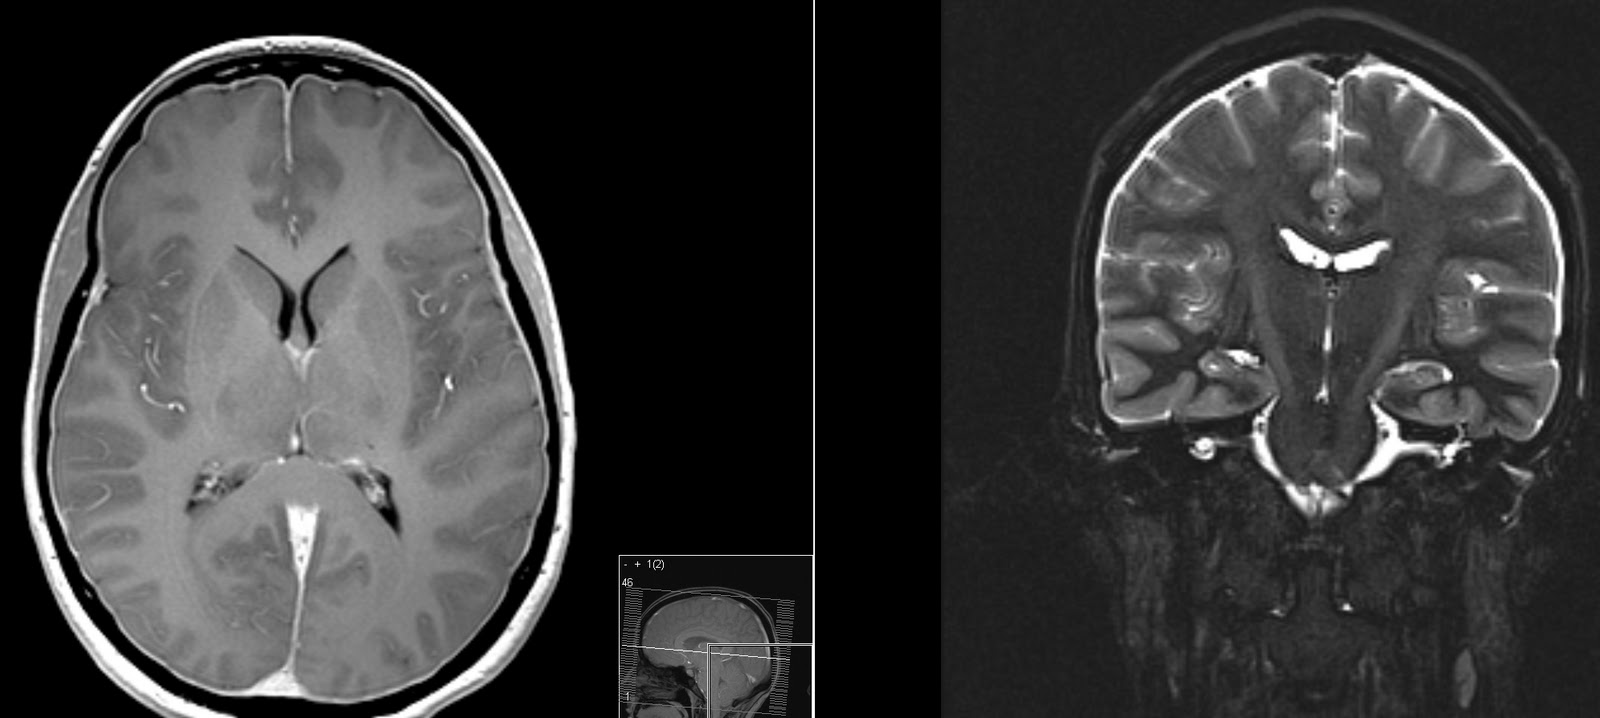

Joey & Hydrocephalus - Special Brain/Hydrocephalus MRI Done ...

The MRI shows there is a "membrane" blocking the flow of cerebrospinal fluid to AND from the brain and spinal cord. Normal pressure hydrocephalus - Duration: 3:44. Andras Fazakas 2,853 views. 3:44 Hydrocephalus, ... View Video